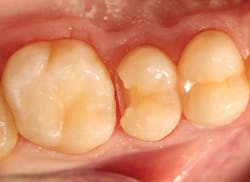

A 19-year-old female presented with a class II lesion on tooth no. 4. After local anesthesia, a conservative slot preparation was accomplished using a #330 pear-shaped carbide, and the remaining caries was removed with a slow-speed round bur (figure 3). A 1–1.5 mm enamel bevel was placed at a 45-degree angle on the occlusal and proximal margins with the very fine flame-shaped diamond (45u) to enhance the enamel etch and marginal seal. The preparation was isolated with a ring-based sectional matrix system (Palodent Plus, Dentsply/Sirona). A selective-etch technique of the enamel margins was employed, and the universal bonding agent was applied according to the DFU. Then, it was light cured for 20 seconds. Omnichroma was placed in two separate increments in the class II preparation, and then condensed and shaped with composite instruments. Each layer was exposed to the LED curing light for 20 seconds from the buccal, lingual, and finally, occlusal. After removal of the ring, wedge, and sectional matrix, the occlusion was checked in the usual manner, and shaping and polishing were completed using the same carbide burs and abrasive cup/point system as the class V restoration in case no. 1 (figure 4).Case no. 3